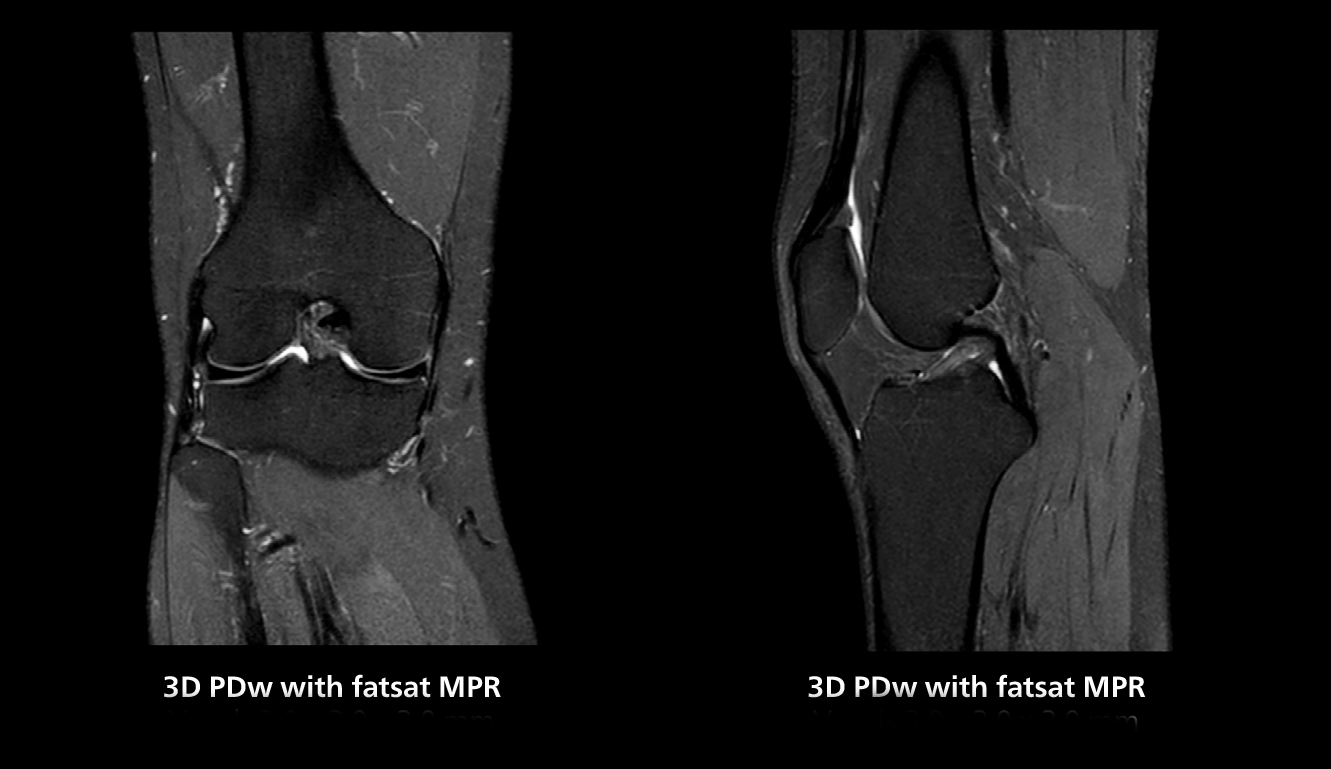

The isotropic high resolution 3D sequence in this MRI case allows for reformatting to obtain other orientations with high quality. Acquired on the MR 5300 system.

“We have more speed in 3D sequences,” Dr. Gellée states. “With Compressed SENSE, we can replace two or three 2D scans withone high-quality 3D scan. High quality additional orientations are then obtained by post-processing of the 3D data set, thus saving scanning time.”